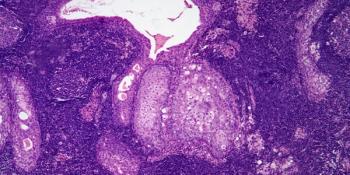

A 35-year-old HIV-positive man presents with enlarged lymph nodes, and a biopsy is performed. What is your diagnosis?